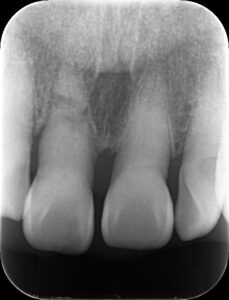

右上の前歯を転倒により強打し、歯根が破折してしましました。

このように深い位置で折れてしまった場合、保存ができないので抜歯が必要となります。